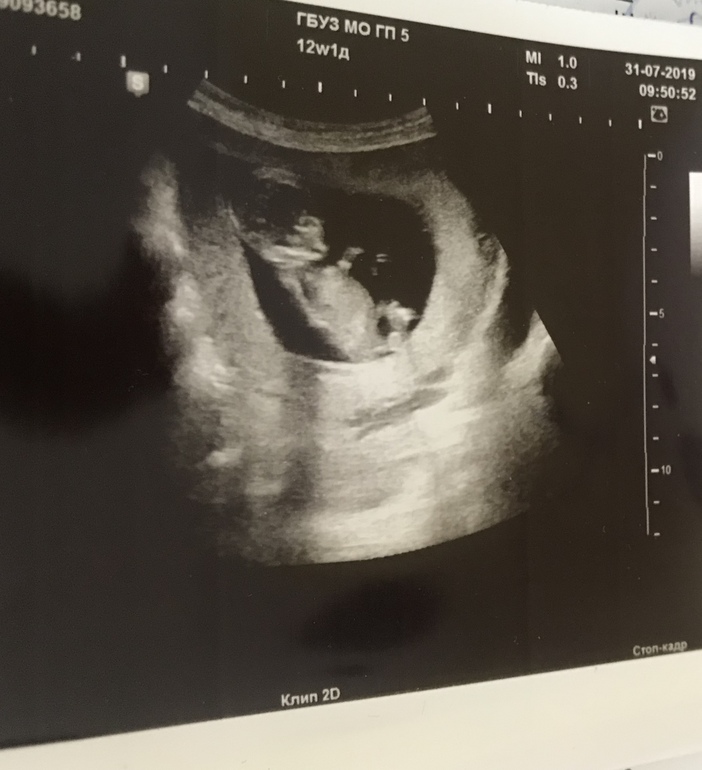

УЗИ 13-ая неделька 🙏🏻

УЗИ, КТГ, доплерДобрый день! Не вытерпела до скрининга, волновалась, так как пришлось совершить срочный перелёт , и ситуация стрессовая была. Побежала на свидание с малышом. Тьфу, тьфу, тьфу! С малышом все хорошо 🙏🏻 Все измерили, показали. Пальчики в рот тянет, пятками брыкается ☺️ Вот только пол предполагать не стали, сказали только, что пока похоже на девочку больше, но легко и перепутать на этом сроке. Попробовала на снимке посмотреть, не самый удачный кадр в этом плане. Не рассмотрела🙈